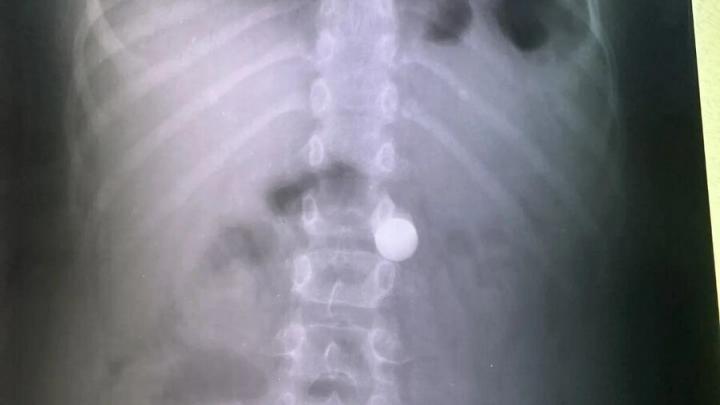

Как сообщает пресс-служба медучреждения, за весь праздничный период поступил лишь один ребёнок с инородным телом. Восьмилетний мальчик проглотил металлический шарик диаметром около сантиметра. Медики успешно извлекли предмет с помощью эндоскопа. Больше подобных случаев за время каникул не зафиксировано.